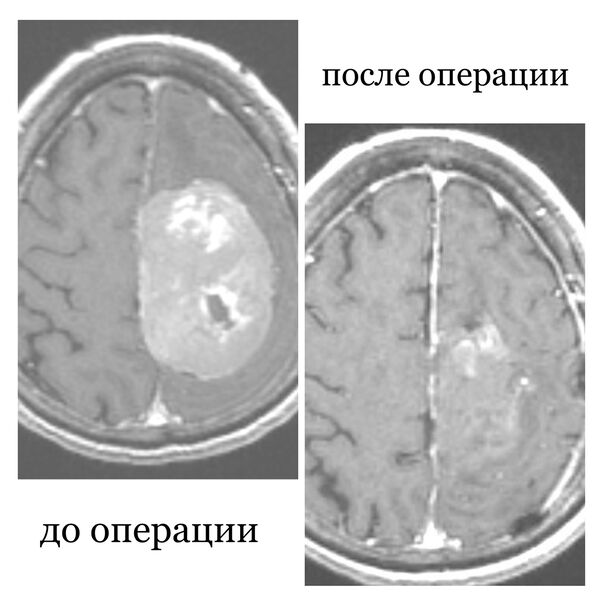

В Республиканской клинической больнице Бурятии медики прооперировали пациентку с опухолью головного мозга, женщина шесть лет отказывалась от хирургического вмешательства. Об этом сообщает пресс-служба медицинского учреждения.

76-летняя пенсионерка поступила в больницу с жалобами на нарушение речи и слабость в конечностях. Врачи установили, что еще в 2018 году у пожилой женщины была диагностирована опухоль головного мозга, однако тогда пациентка отказалась от операции и не стала продолжать лечение.

«При поступлении пациентка уже не могла двигаться, была нарушена речь, сознание спутанное. Мы сразу же приступили к противоотечной терапии. Переговорили с родственниками и они, наконец-то дали свое согласие на операцию», — сообщил нейрохирург республиканской клинической больницы Булат Цыбиков.

Хирургическое вмешательство прошло успешно, спустя неделю после операции пенсионерку выписали на амбулаторное лечение.